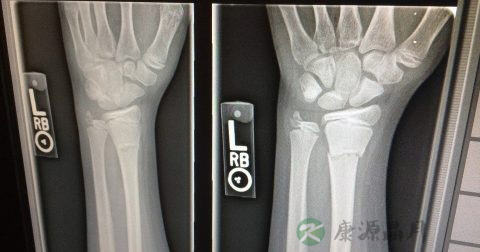

同位素扫描过程中所接受的辐射剂量与一般诊断放射用的X-光相若,基本上所用放射性药物不会带来后遗症,检查后、病人可以如常工作。